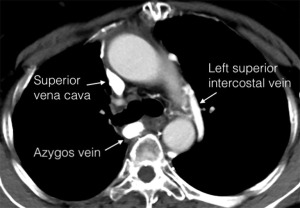

A 57-year-old female patient was admitted to Shanghai Chest Hospital in November 2020 with an anterior mediastinal mass after a B2 thymoma resection 8 years before. Chest computed tomography (CT) revealed an 84mm right anterior mass invading the right lung, bilateral innominate veins, and SVC, with tumor embolism inside the SVC (Figure 1A). Core needle biopsy suggested recurrence of B2 thymoma. After sequential chemoradiotherapy (SCRT), the patient had partial response (PR) and CT revealed the tumor still invaded the right lung, bilateral innominate veins, and SVC, but tumor embolism was not obvious (Figure 1B). The left superior intercostal vein ran down the left side of the aortic arch from the left innominate vein to the azygos vein (Figure 1). The azygos was not invaded by the tumor.

The patient underwent median sternotomy with preparation for SVC reconstruction in April 2021. A right internal jugular vein catheter was placed to monitor IJVP. A radial arterial line was inserted to monitor the systemic blood pressure during surgery. The mass invaded the right upper lobe, bilateral innominate veins and SVC. The enlarged left superior intercostal vein originated from left innominate vein and descended along the left lateral side of aortic arch and joined the azygos vein (Figure 2A). IJVP was found to be 29 cmH2O after clamping the SVC. The tumor and the invaded structures were removed without SVC reconstruction and the azygos vein was reserved (Figure 2B). No obstructive complications were found postoperatively. Operation time was 167 minutes and blood loss was 1,000 mL. The patient started to ambulate on the 2nd postoperative day and was discharged 8 days after surgery. Pathological examination showed mixed thymic carcinoma with 20% thymic squamous cell carcinoma and 80% B2 thymoma. The tumor invaded pericardium, lung, SVC and bilateral innominate veins.

Collateral circulations may develop after chronic SVC obstruction (11). In case 1, preoperative imaging showed that the patients had an obvious collateral vein on the left side of the aortic arch originating from the left innominate vein but it was hard to know if the collateral circulations could completely compensate for the loss of the SVC-innominate vein route. So, we prepared for venous reconstruction before surgery and used intraoperative IJVP to decide whether to perform the reconstruction. We also found a thick collateral vein (left superior intercostal vein) consistent with the imaging intraoperatively (Figure 2B). IJVP was below 30 cmH2O when clamping the SVC, supposing adequate blood return to the heart. Therefore, SVC and bilateral innominate veins were resected without venous reconstruction, while azygos vein were reserved. In case 2, the tumor invaded inside the SVC and azygos vein was also invaded. When clamping the SVC and azygos vein, IJVP was also below 30 cmH2O and therefore SVC, bilateral innominate veins and azygos vein were resected without venous reconstruction. These patients recovered well postoperatively without severe obstructive complications. Long-term follow-up showed more abundant collateral circulations and no recurrence of tumor.